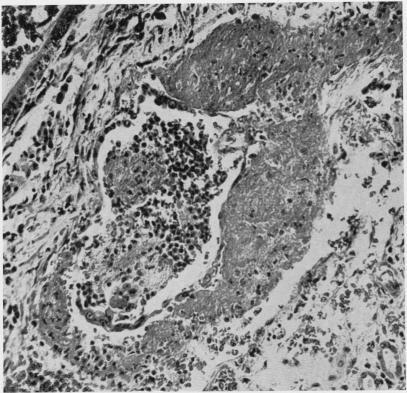

Distal tubular and proximal tubular necrosis in the kidneys of burned patients.